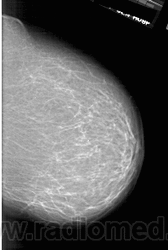

Со старением железистая ткань постепенно исчезает: прозрачность жировой ткани становится преобладающей с несколькими каркасами, связанными с опорными волокнистыми структурами.

Жирная (не плотная) грудь

Умеренно плотная грудь

Плотная грудь

Маммограммы представляют собой изображения структур, проецируемых на плоскость: плотная грудная маммограмма, следовательно, состоит из многих других структур, которые необходимо проанализировать, чем более жирная, пустая грудь. По этой причине диагностировать рак молочной железы труднее для моложе, чем для пожилых женщин.

Нажмите на миниатюрные картинки, чтобы получить увеличенный размер.